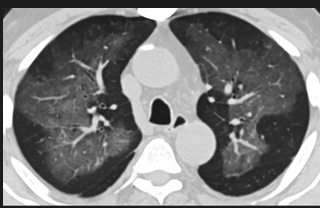

更值得注意的是,有之前应对过武汉新冠疫情的中国权威肺病专家,在查阅了60篇涉及美国“电子烟肺病”病例的研究论文,并对其中142位电子烟肺病患者的250张肺部影像图片、临床信息以及文献原文进行了仔细全面的研究后,发现这些病例中有16个更有可能是新冠肺炎的“疑诊患者”,有5个临床症状和治疗情况相对完整的患者,还被这些专家认定为了“中度可疑”。另外,这16个病例中有12个病例的发病时间,都在2020年以前。

(这4张图,是专家怀疑被误诊为电子烟肺病的其中一个病例的肺片。专家表示,他们不是仅仅通过一张影片做判断的,而是通过这4张涵盖了这名病例肺部多天变化情况的影片进行的研判,认为该病例的病程进展跟新冠更为相似)